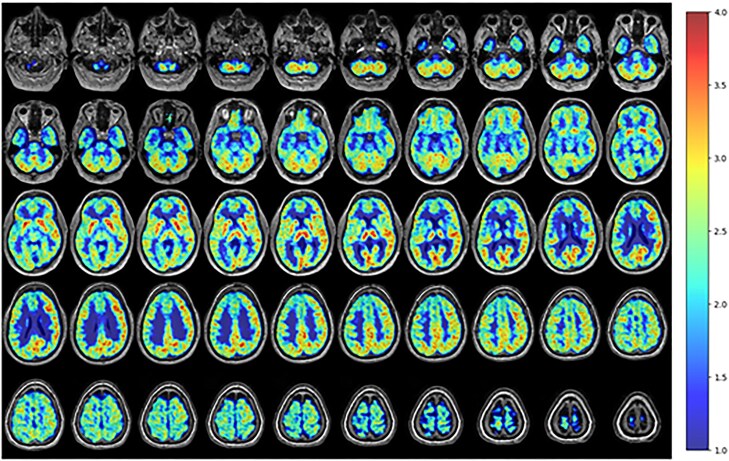

Case presentation: Our participant is a 58 year-old male with a past medical history notable for alcohol use disorder and BD (unspecified type) who underwent PET imaging with the mitochondrial complex I PET ligand 18F-BCPP-EF. The resulting images demonstrated significant overlap between areas of dysfunction identified with the 18F-BCPP-EF PET ligand and prior functional magnetic resonance imaging (MRI) techniques in the setting of BD. That overlap was seen in both affective and cognitive circuits, with mitochondrial dysfunction in the fronto-limbic, ventral affective, and dorsal cognitive circuits showing particularly significant differences.

Abstract Image